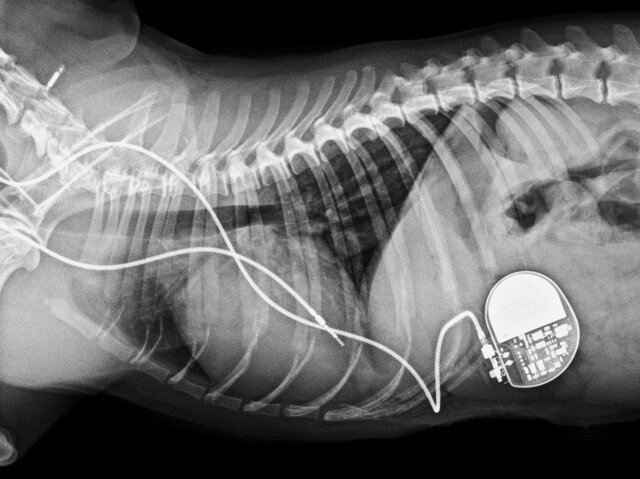

Arne Larson

La electricidad salió del terreno de la charlatanería y se convirtió en una herramienta médica legítima, Arne Larson un ingeniero sueco se convirtió en uno de sus primeros beneficiarios.

• Marcapasos cardíaco artificial

Marcapasos cardíaco artificial

Arne Larson contrajo una infección viral que afectó el funcionamiento de su corazón llevándolo a usar una máquina que mandaba un choque eléctrico a su pecho para poder mantenerlo con vida.

• Marcapasos cardíaco

Marcapasos cardíaco

Se estaba experimentando en animales el crear un marcapasos cardiaco que pueda ser implantado dentro del cuerpo.

• Primer prototipo de un marcapasos

Primer prototipo de un marcapasos

Después de la insistencia por parte de la esposa de Arne Larson, en la mañana del 8 de octubre de 1958: Se implantó el primer prototipo de un marcapasos. Luego de unas horas falló el marcapasos y al día siguiente lo remplazaron pudiendo continuar con su vida , cambiando cada cierto tiempo el marcapasos.